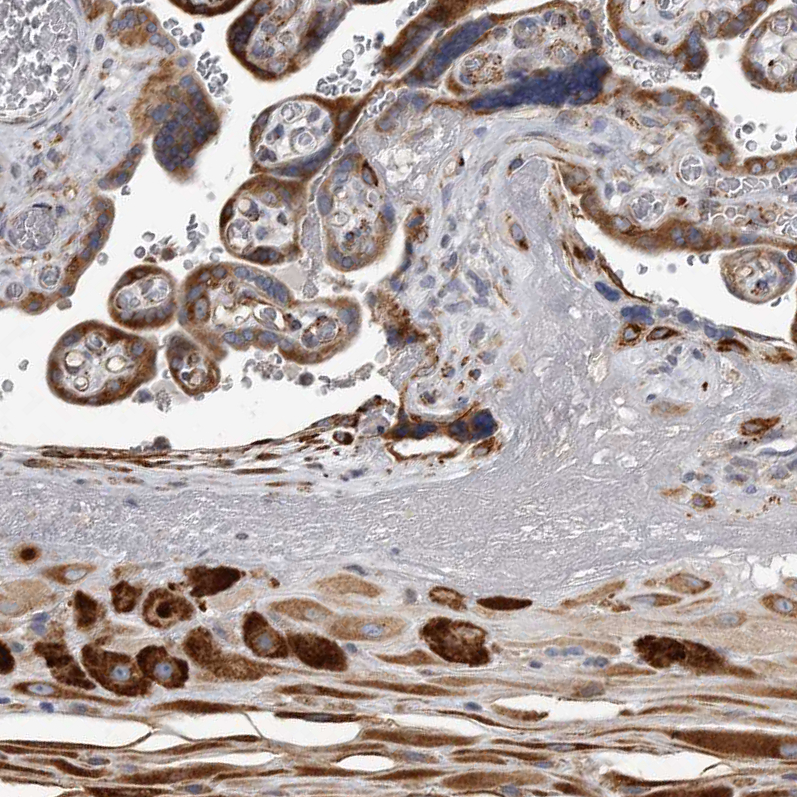

Immunohistochemical staining of human placenta shows strong cytoplasmic positivity in trophoblastic and decidual cells.